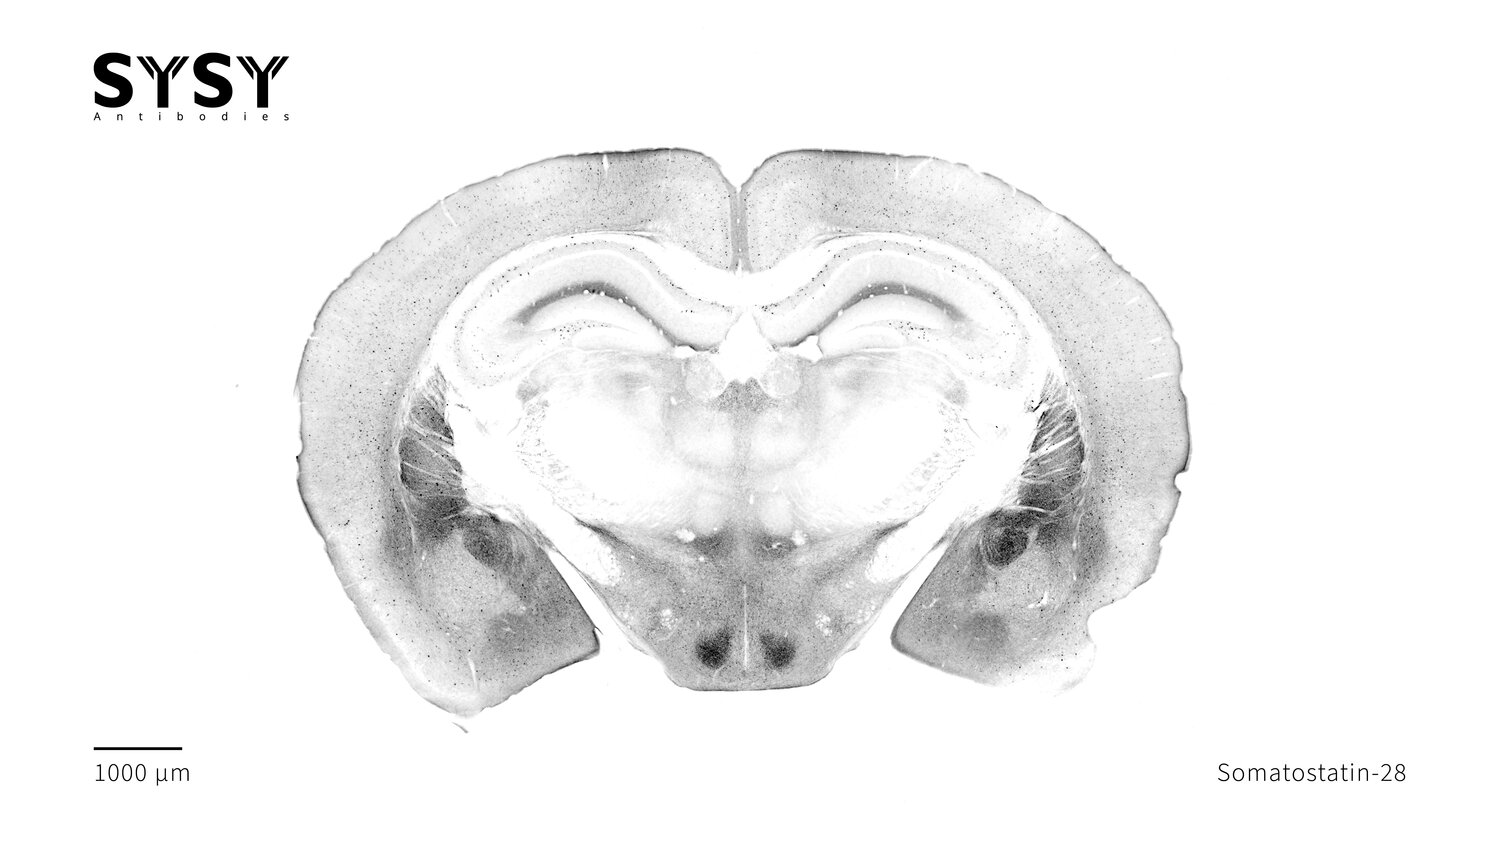

Somatostatin-28

Indirect immunostaining of a formaldehyde fixed coronal mouse brain section with rat anti-Somatostatin-28 antibody (cat. no. 366 017, dilution 1 : 500).